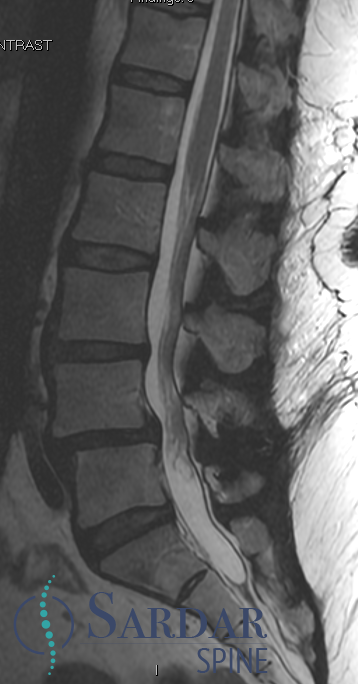

55F with back pain and neurogenic claudication. Despite PT and epidural injections, relief is temporary. Difficulty walking long distances due to pain. What treatment would you offer next? #MedTwitter #SpineHealth #NeurogenicClaudication #spine

Case 1, Part 2: The patient had a #Vertiflex procedure done elsewhere; symptoms worsened, now can't stand upright, uses walker. Thoughts on her treatment so far? Next steps? #MedTwitter #Orthopedics #orthopedicsurgery #neurosurgery #spine #spinehealth #spinesurgery #scoliosis

Case 1, Part 3: For our patient with worsening #spondylolisthesis, We chose L3-S1/ilium reconstruction with TLIF L4-S1. Great news! She can now stand upright without needing a walker. 🌟🩺 #SpineSurgery #BackPainRecovery #MedicalCommunity